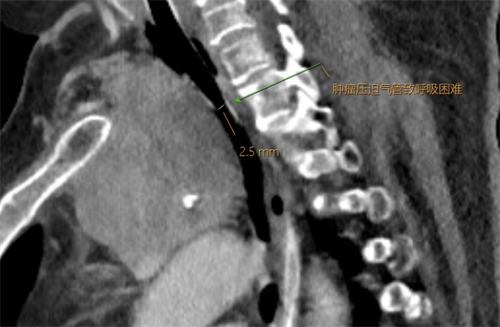

术前CT显示:纵膈巨大占位大小约为10.2cm*9.0cm*8.5cm,邻近气管及大血管明显受压变窄,气管前后径仅为2.5mm(正常成人气管直径约15-25mm)

据了解,李奶奶曾被诊断患有胸腺瘤,多次前往四川省人民医院及四川大学华西医院就诊。由于其身体基础状况较差,且肿瘤巨大(已侵犯大血管及气管),外科切除难度极大,手术风险极高,李奶奶本人也拒绝外科手术切除。此次,因巨大的胸腺肿瘤同时压迫气道和右侧无名静脉,导致李奶奶出现急性呼吸困难和上腔静脉血液回流受阻而昏倒。

术前患者呼吸困难(气管受压插管)、颜面部水肿(上腔静脉阻塞)